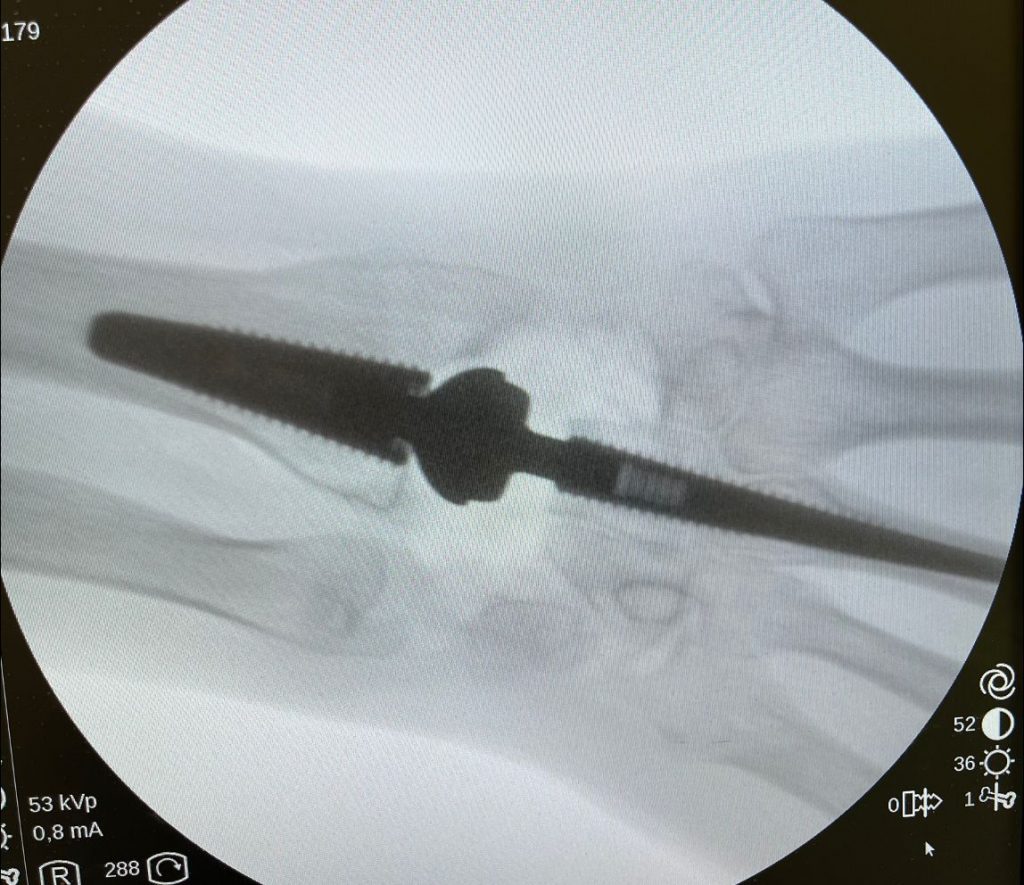

PATOLOGIAS MUÑECA - PRÓTESIS ARTICULARES Figura 2 - Prótesis total de Articulación Radio-Cubital distal

Figura 2 - Prótesis total de Articulación Radio-Cubital distal.